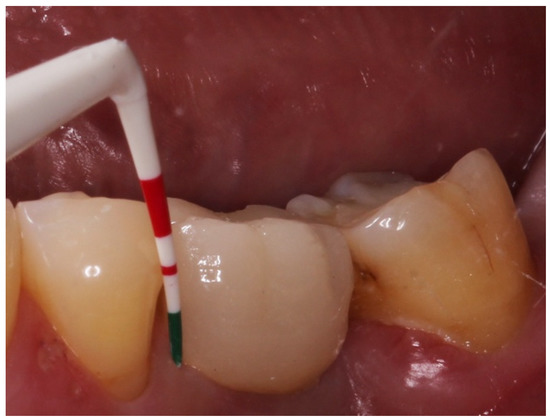

Retrospective Study of the Association between Peri-Implantitis and Keratinized Mucosa

- The presence of KM around the implants seems to have been associated with peri-implantitis and with a transparency of the peri-implant tissues.

- The absence of KM appears to have an impact on certain clinical parameters: Recession is augmented in implants with absence of KM; hygiene is facilitated when implants are surrounded by KM, therefore the plaque index is lower; probing depth tends to increase in implants without KM; bleeding and suppuration are reduced in the presence of KM and bone level tends to be lower in implants without KM.